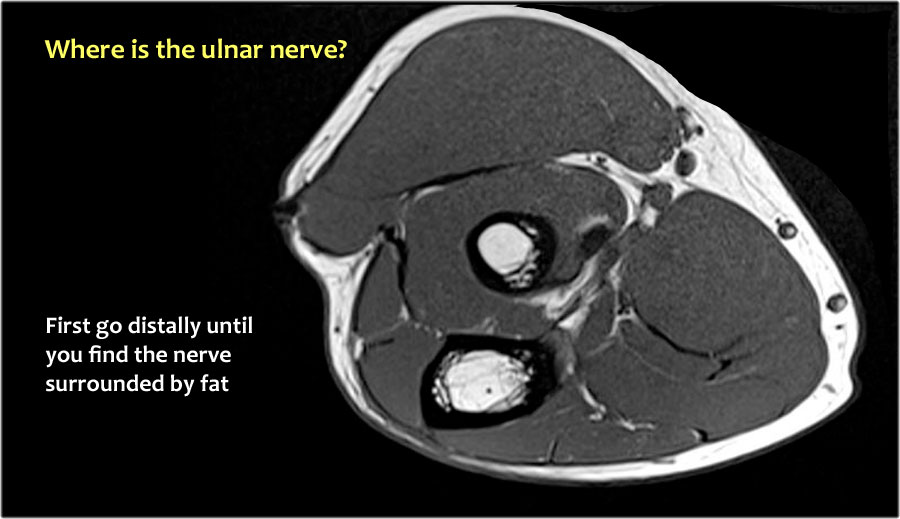

Vì vậy, khi chúng ta quay lại hình ảnh, bạn sẽ nhận thấy rằng có thể khó tìm thấy dây thần kinh.

Bất kỳ cấu trúc dưới da nào trong số này đều có thể là dây thần kinh đã được chuyển vị.

Một cách để thực hiện là đi theo các cấu trúc về phía xa cho đến khi tìm thấy dây thần kinh trụ ở phía xa tại vị trí bình thường của nó ở vùng cẳng tay gần được bao quanh bởi mô mỡ.

Sau đó khi bạn theo dõi nó về phía gần, bạn sẽ nhận thấy rằng đây là một trường hợp chuyển vị dưới da.